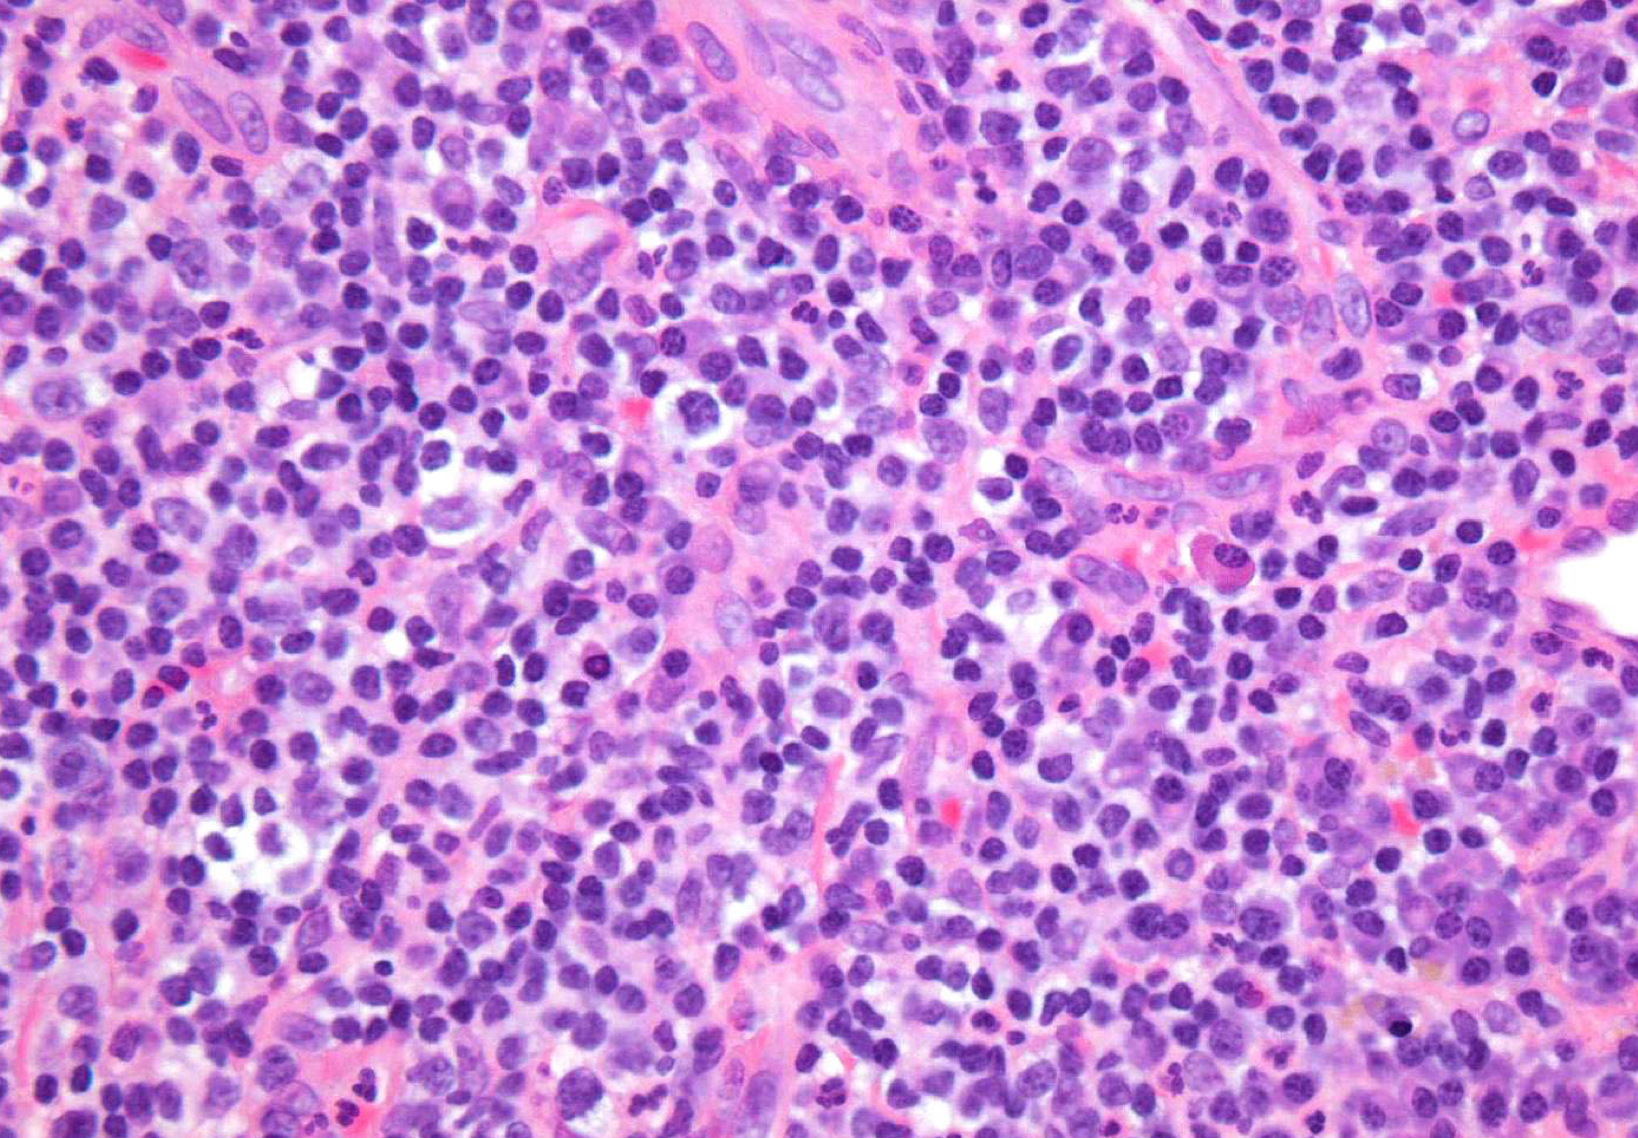

histopathological features:Â

granulation tissue surrounded by fibrous CT

tissue from apex of non-vital tooth socket

lymphocytic infiltrate may be intermixed w neutrophils, plasma cells, histiocytes, and occasionally mast cells or eosinophils Â

periapical granuloma

periapical granuloma; granulation tissue w neutrophils, lymphocytes, plasma cells, vascular channelsÂ

which potential result of periapical inflammation?

periapical granuloma; fibroblasts

periapical granuloma; lymphocytes